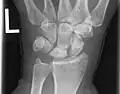

Left hand x-ray with Kienbock's Disease showing 4 mm negative ulnar variance and Kienbock's Disease Stage IIIB

Left hand x-ray with Kienbock's Disease